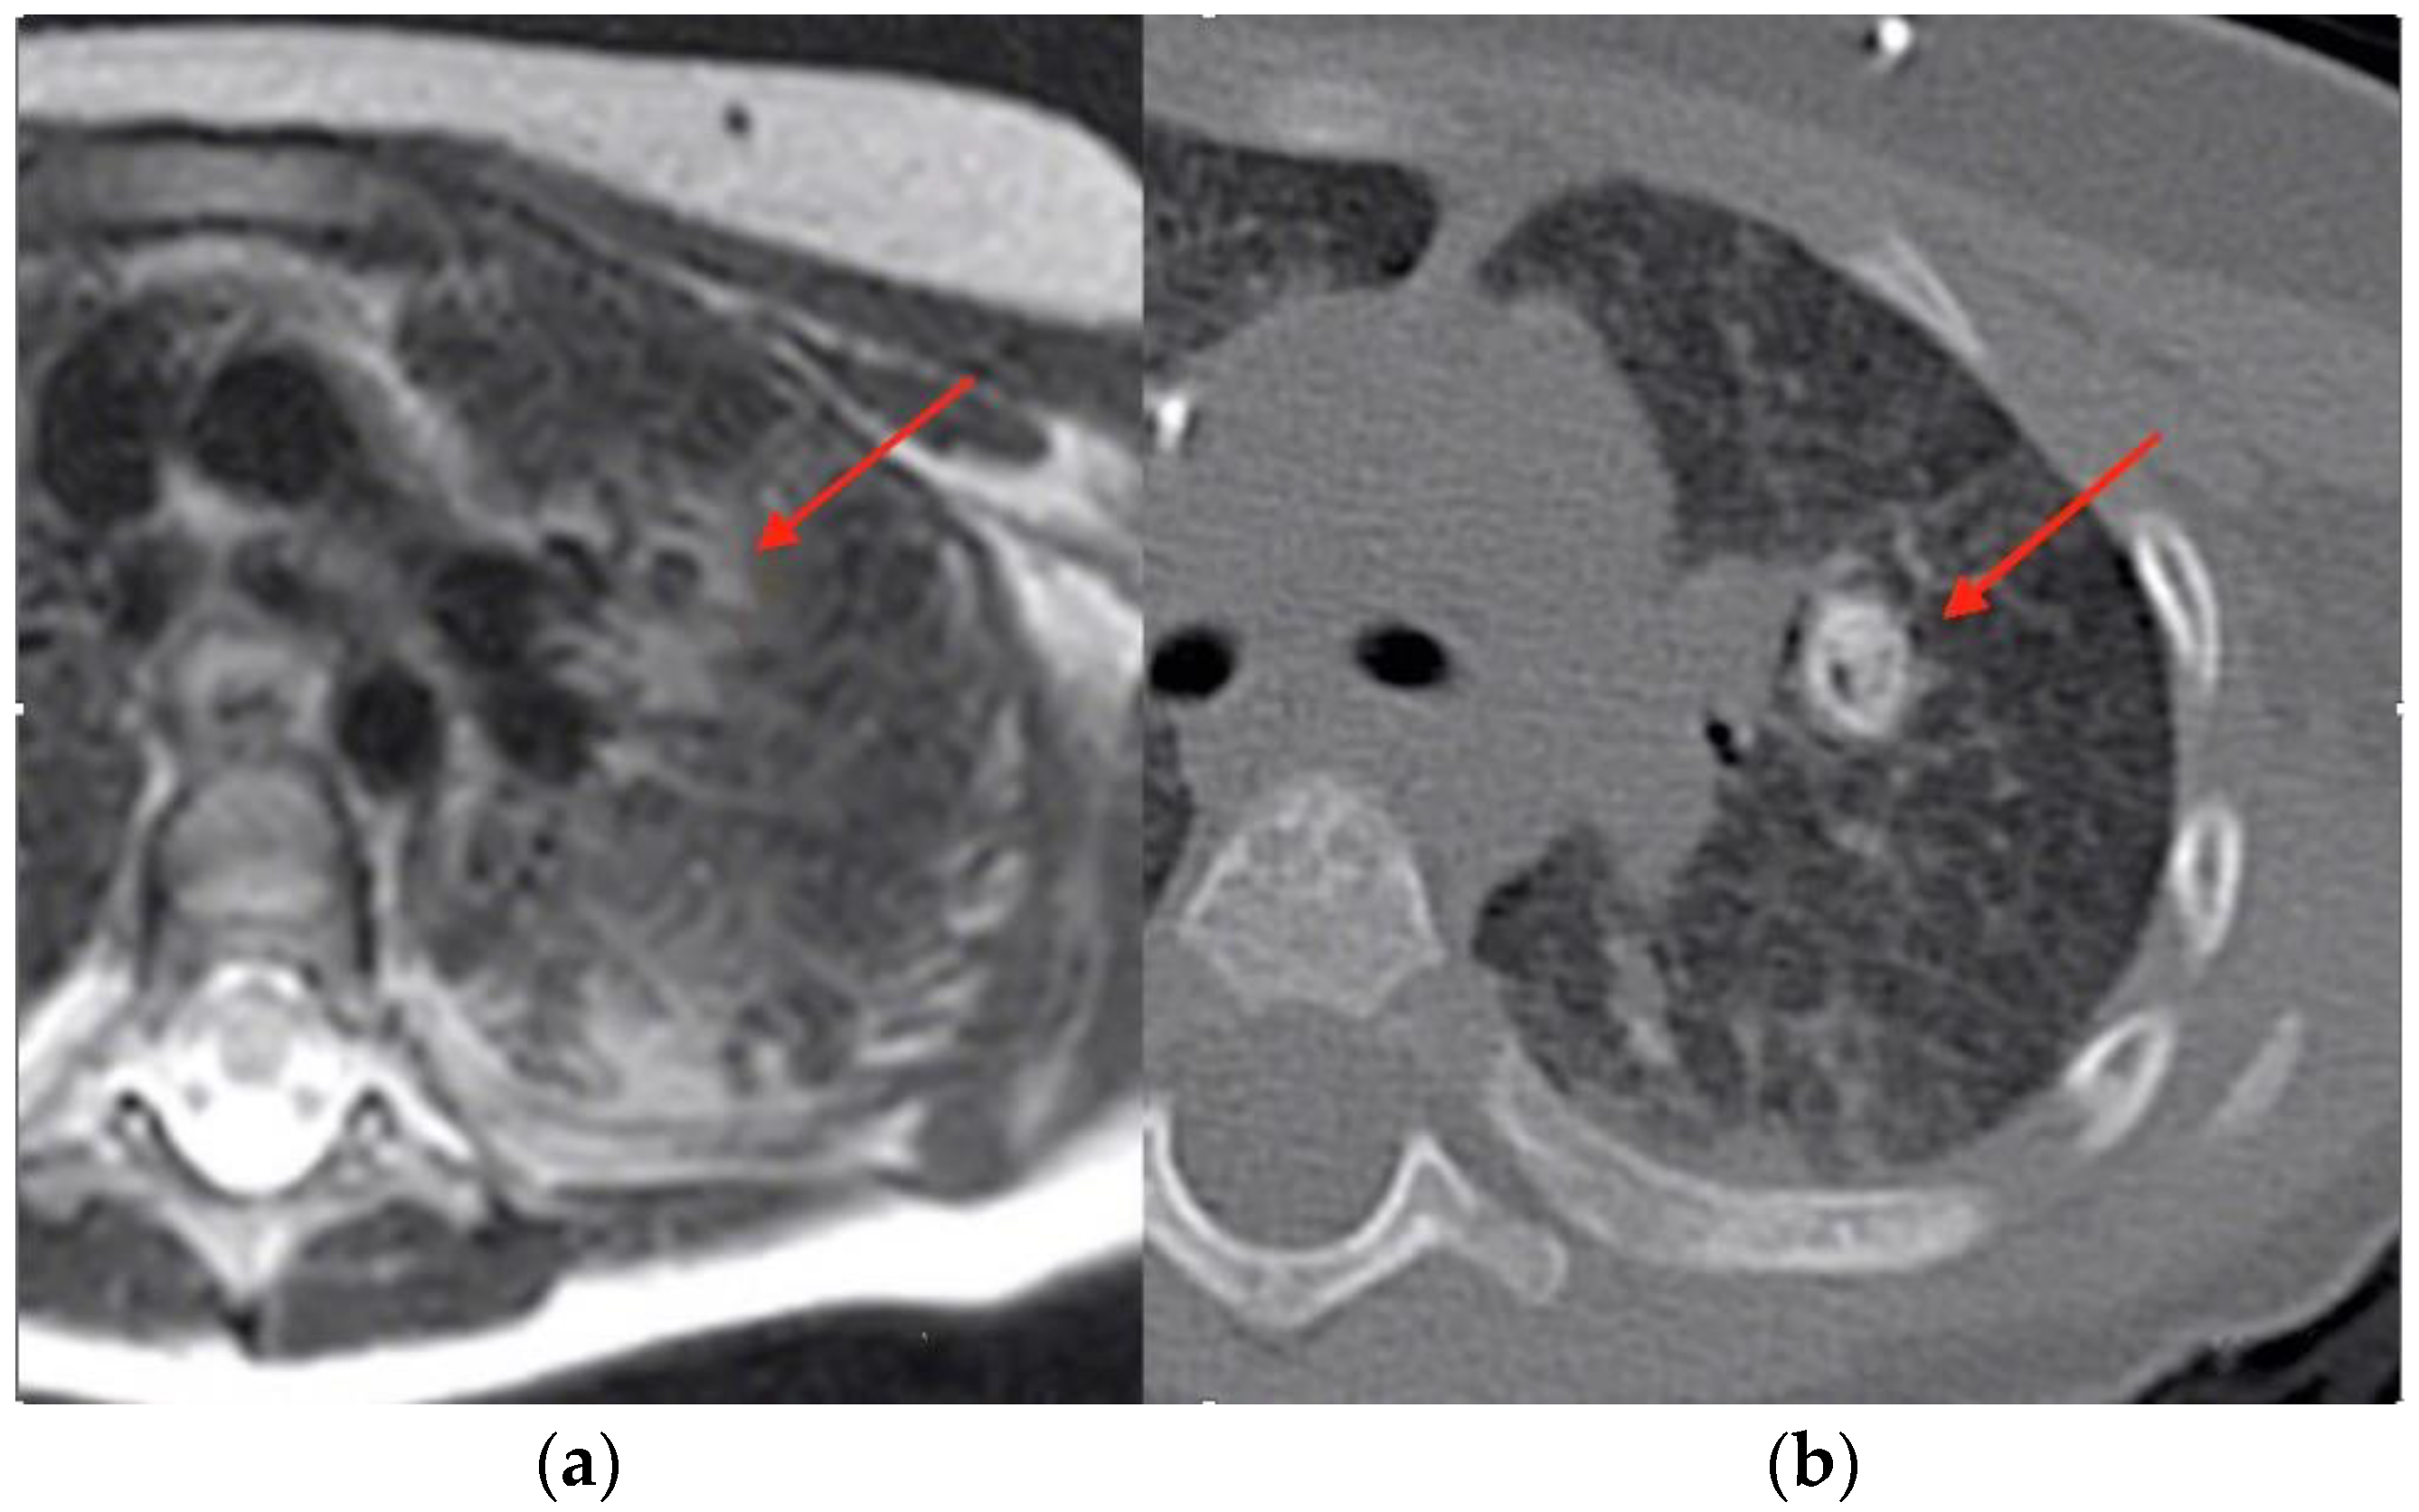

At age 9 months, prior to HSCT, he underwent a routine total-body magnetic resonance imaging (MRI). The examination was performed using an open bore 1,5T machine, Philips Ingenia. The sequences used for whole-body MRI are coronal T1 and T2 weighted and axial diffusion. A T2 HD axial sequence performed to study lungs showed significant alterations of the pulmonary parenchyma characterized by pulmonary consolidations and two cystic, thin-wall lesions. A CT (Philips Brilliance 40CT scan) of the lung was performed subsequently, showing the presence of 11 calcified granulomatous nodules. The calcifications were distributed perihilar and peripheral, both where previously consolidations were present, particularly the larger ones. (Figure 1 and Figure 2).

Figure 1. (a) MRI showing the presence of an unclear pulmonary lesion (indicated with the arrow); (b) CT scan distinctly showing a pulmonary calcification (indicated with the arrow) which was not clearly seen on MRI.